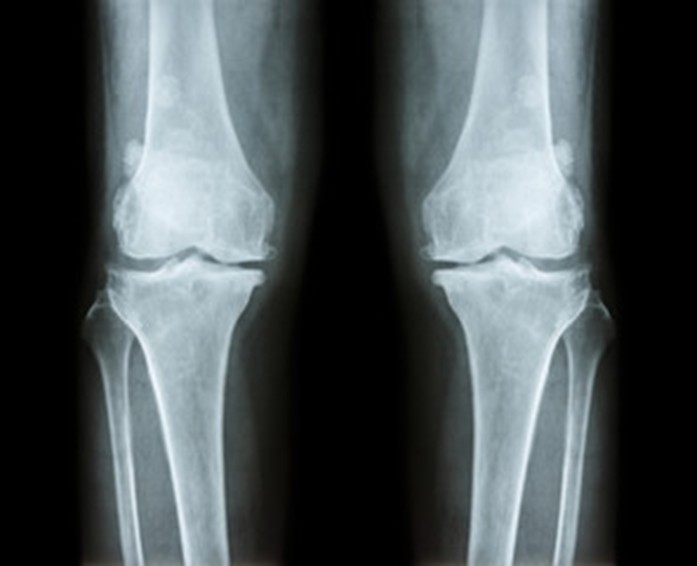

1. Radiografia

É o exame fundamental: mostra estreitamento articular, osteófitos e deformidades.

Deve ser efectuado sempre em carga para não subestimar o desgaste.